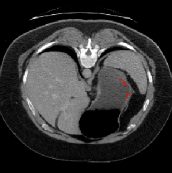

To validate the effectiveness of our method, we conducted experiments on two representative publicly available datasets: SABS [24] and CMR[25]. The SABS dataset originates from the Multi-Atlas Abdominal Label Challenge released by MICCAI2015. It comprises CT scans of the abdomen with multi-organ segmentation, featuring organs such as the pancreas, kidneys (left and right), gallbladder, adrenal glands (left and right), liver, and inferior vena cava, among others. This dataset consists of 30 3D CT scans. The CMR dataset, on the other hand, is a cardiac segmentation dataset published by MICCAI in 2019. It encompasses 35 scans, each with approximately 13 slices per scan.

To ensure fair comparison with other methods, we employ a consistent setting by adjusting all images to either 2D axial or 2D short-axis. Specifically, for the SABS dataset, we convert it to a 2D axial representation, while for the CMR dataset, we transform it to a 2D short-axial format. Subsequently, all adjusted images are resize to 256×256 size. Focusing on the SABS dataset, akin to prior approaches, we concentrate our analysis on the model’s performance concerning the kidneys, liver, and spleen. Furthermore, all experiments follow a five-fold cross-validation methodology.

Table 1 presents the model and other methods’ performance on the SABS dataset, while Table 2 displays their performance on the CMR dataset. Our model exhibits superior performance across both settings, as illustrated in Table 1. Specifically, under Setting 1, our model achieves an average Dice score of 77.00%. Notably, in liver organ segmentation, our model outperforms ALPNet and QNet by 6.50% and 4.09%, respectively.

Figure 3 illustrates the specific segmentation results on the SABS dataset under Setting 1. Our model demonstrates higher accuracy in segmentation and effectively reduces unnecessary segmentation. Even under Setting 2, where the test class is entirely invisible to the model, our model performs well, as depicted in Figure 4. Given that SABS is a multi-organ dataset with many organs of small size, precise segmentation proves challenging. However, our model excels, particularly in the scenario of completely invisible classes, which closely resembles real-world conditions. Figure 4 highlights our model’s ability to accurately segment very small target organs, such as the right kidney. In contrast, the ADNet method fails to produce effective segmentation predictions, and other methods exhibit varying degrees of over-segmentation. On the CMR dataset, as shown in Table 2, our model generally outperforms others.